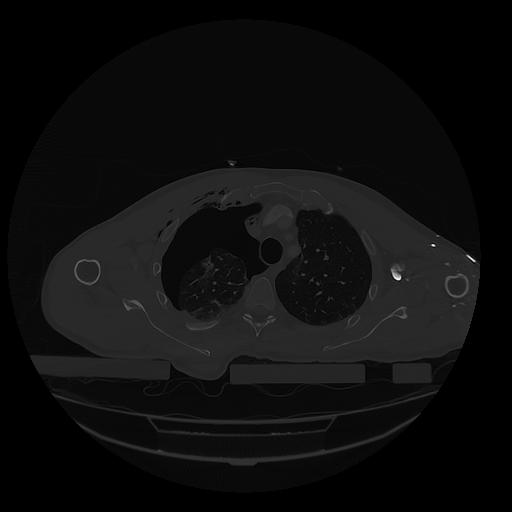

31 PULMON,CE,Vol,1.0,PULMON,,